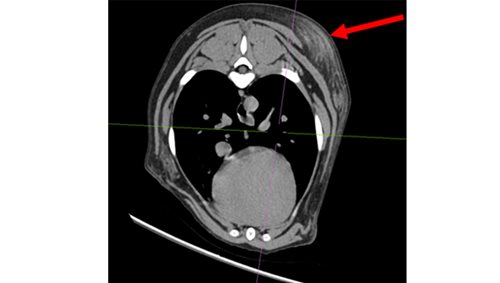

We decided to perform a positive contrast CT scan of the thorax, abdomen and pelvic limb. We also performed a sinogram: injection of contrast into the sinus to outline and define any communications of the draining sinus and a potential foreign body.

This CT scan identified three lesions – the draining wound on her flank (which communicated to a suspected abscess under her spine), a nodule in her armpit/axilla and a third mass immediately behind her scapula.

Left image: Orange area – fluid pocket ventral to spinal vertebrae, Red area – subcutaneous mass on left flank